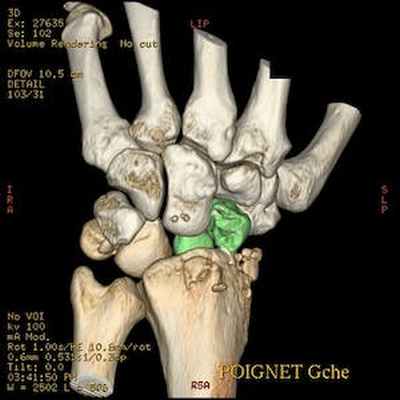

Трансладьевидно-перилунарный вывих запястья III-его типа

Трансладьевидно-перилунарный вывих запястья (перелом ладьевидной кости в виде основной сагиттальной линии, с образованием двух сильно смещенных фрагментов; проксимальный фрагмент остается в нормальном соотношении с полулунной костью; разъединение костей первого и второго ряда запястья).

Наличие мелких костных фрагментов вокруг трехгранной кости вместе с отрывными переломами; смещение кзади трехгранной кости.

Оскольчатый перелом шиловидного отростка лучевой кости.

Локтевая кость цела.